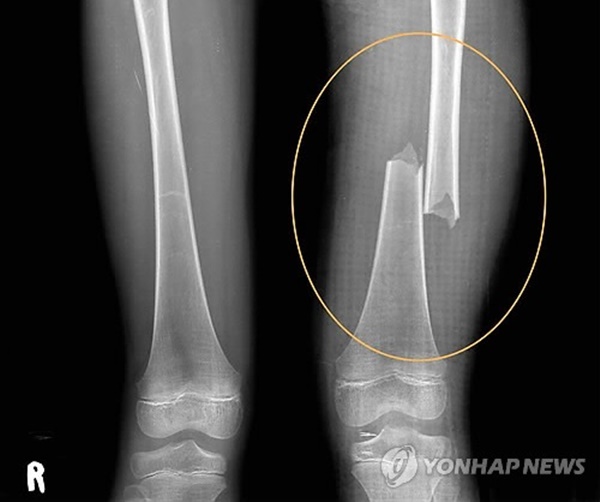

Vào ngày 21/5/2012, Park đã đập vào đùi của bé Lee nhiều lần khiến cho đứa trẻ bị gãy xương, phải mất 10 tuần điều trị mới hồi phục. Nguyên nhân chỉ bởi vì bé Lee về nhà muộn 10 phút nhưng câu chuyện lại bị Park che đậy bằng lời nói dối, rằng đứa trẻ bị ngã xuống cầu thang ở trường.

Tiếp đến, Park còn bắt con nhỏ đứng vào bồn tắm chứa đầy nước nóng với mục đích... làm mờ những vết thâm tím. Nhưng thời điểm đó, bé Lee đã bị đánh đến nỗi bị gãy 16 chiếc xương, một trong số đó đâm vào phổi đứa trẻ, gây ra tình trạng xuất huyết nội, dẫn đến khó thở và tử vong. Kết quả khám nghiệm tử thi cho thấy các cơ vùng mông của bé Lee biến mất, xuất hiện triệu chứng xơ hóa mô, xảy ra khi nạn nhân bị đánh trở lại trước khi các mô tổn thương lành hẳn.